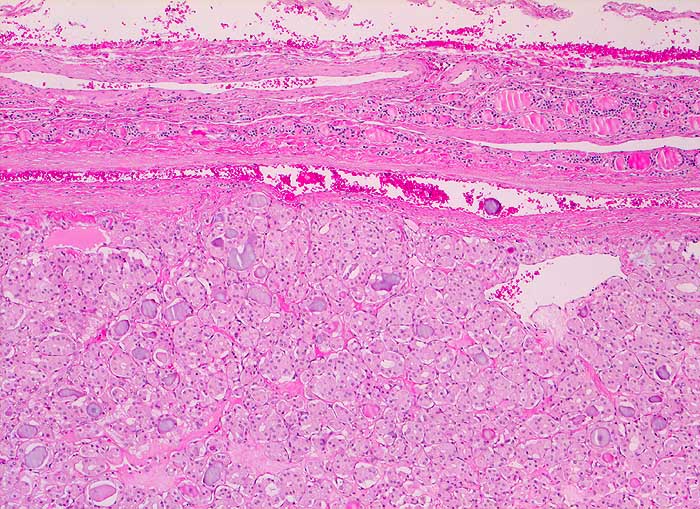

Einleitung

Punktate aus mikrofollikulären oder trabekulären Adenomen sind zellreich und kolloidarm. Die Thyreozyten bilden oft Mikrofollikel oder kleine Rosetten, die eosinophile Kolloidtropfen umschliessen. Die Kerne sind gleichförmig rund, fein granuliert und zeigen keine Atypien. Gelegentlich finden sich regressive Veränderungen. Zytologisch sind follikuläre Adenome und hoch differenzierte follikuläre Karzinome nur schwer zu unterscheiden. Aus diesem Grund werden beide Läsionen mit dem Begriff "follikuläre Neoplasie" bezeichnet. Unten sind zwei Beispiele von mikrofollikulären Adenomen abgebildet.